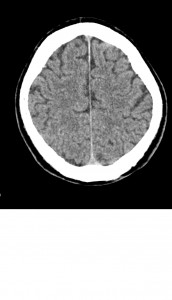

El TAC de cráneo sin contraste sería la prueba de elección en primer lugar ya que nos proporcionará información a cerca de si la lesión es isquémica o hemorrágica para de esa manera poder decidir si se le aplica al paciente un tratamiento trombolítico o no. Se realizaría sin contraste porque debido a que en la fase aguda del ictus la sangre es hiperdensa no se podrían valorar las lesiones hemorrágicas.

En segundo lugar también es útil para descartar otras causas no vasculares causantes del cuadro clínico como un traumatismo o metástasis.